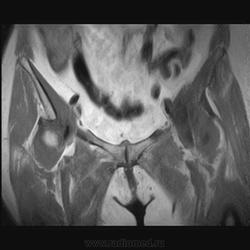

Пациентка 1944г. р. Жалобы на боль области сустава в течении месяца. Температуры не отмечала. Серьезных травм со слов не было. Внешний осмотр новых данных не дал.

Дайкомы пока не смотрела-скорость интернета дома небольшая.Думаю, что здесь проблемы в суставе и параартикулярных мягких тканях.Не так давно у меня что-то похожее было.

типа бурсита тазобедренного сустава? подвздошно-гребешковая сумка получается

А как вам стенка прямой кишки?

Да, еще подвздошная область.

Подозрительная, но неубедительно пока.Ни одного сагитталла не вижу с прямой кишкой.Нужно дообследовать однозначно.